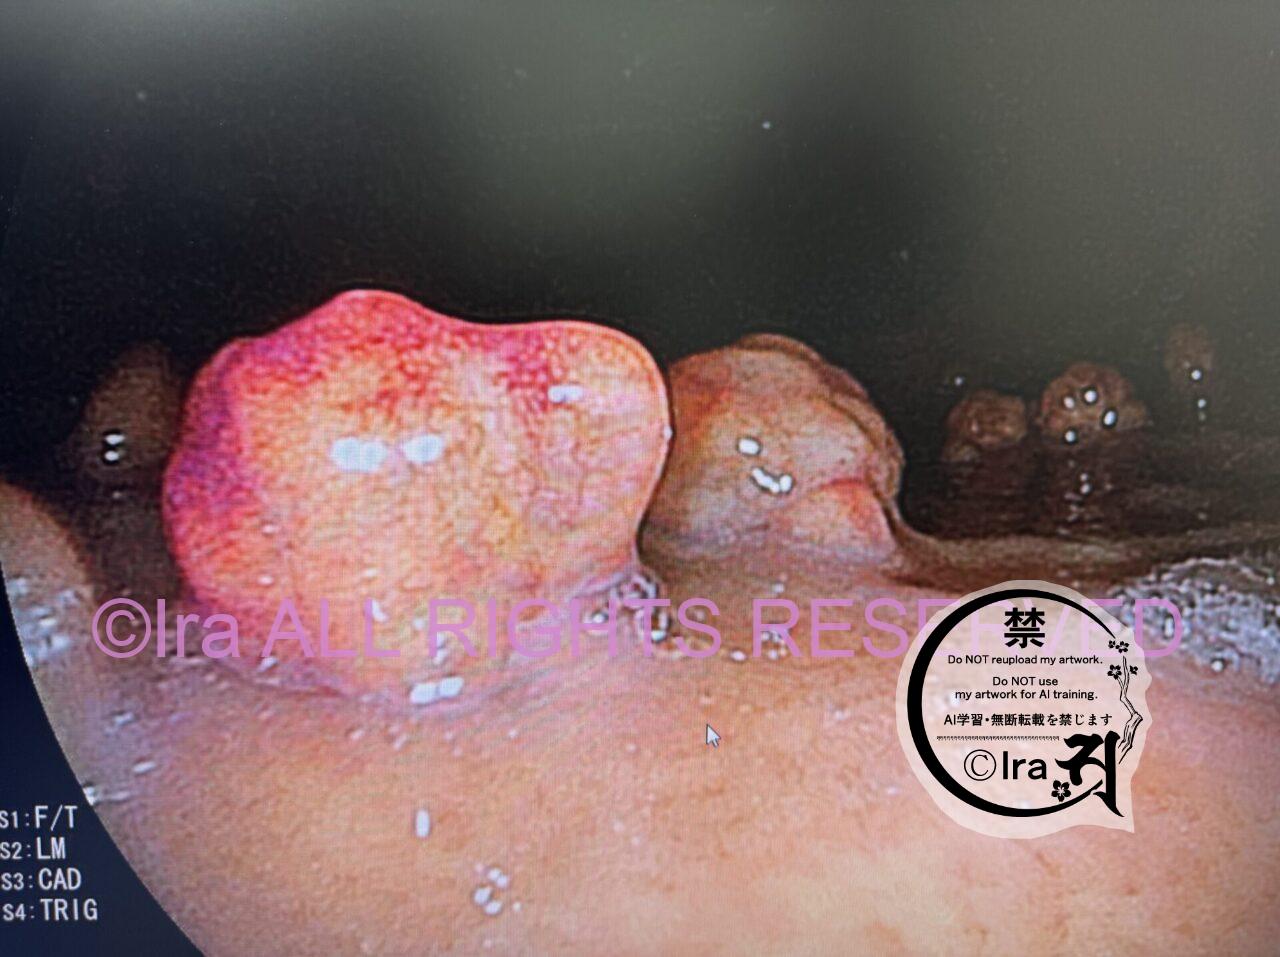

そんなIraの胃カメラ写真。ポリープは50個超え。

2025年撮影。

こんなポリープだらけの胃に食べ物が入ってくる。

日本では僕の胃にポリープの森ができました。

医者は「50個以上数えるのは大変なので」と白旗あげてました。